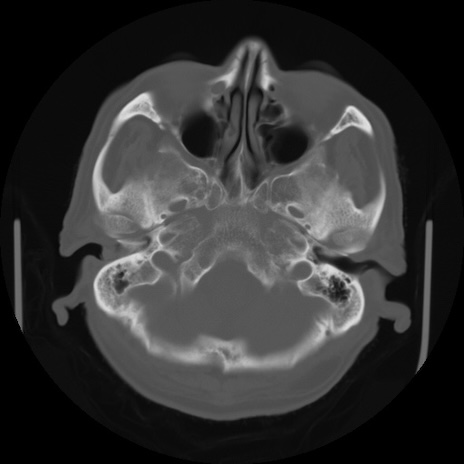

【頭部】症例5 CT(横断像)

CT(矢状断像)

【症例】80歳代 男性

【主訴】頭部打撲

【現病歴】外出先で椅子から立ち上がる際に、つまづいて後方へ転倒し受傷。転倒時に意識はあった。

【身体所見】BP 217/71、HR 96、JCS1-1、 難聴あり、顔色良好、右後頭部に擦過創あり。神経学的異常なし。

症例5の画像所見と診断は?